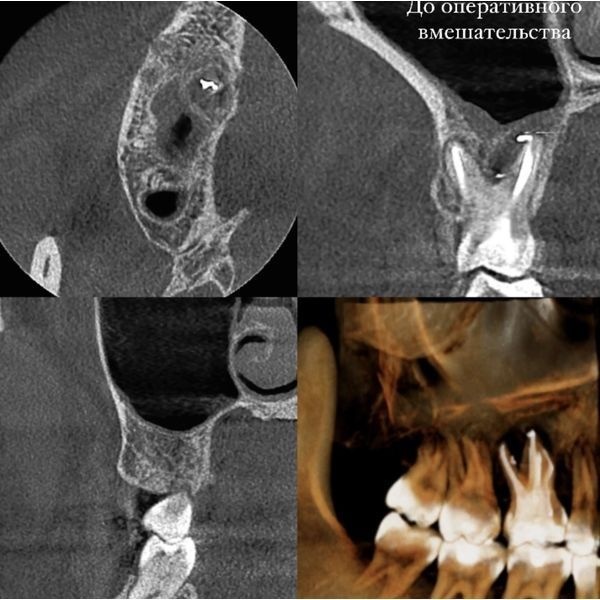

Компьютерная томография (КТ) зуба 1.6 показала, что пломбировочный материал вышел за пределы корневого канала в область вокруг верхушки корня зуба и мигрировал в область фуркации — пространства между корнями моляра, где он покрылся соединительной тканью (инкапсулировался), которая продолжила разрастаться дальше. Это привело к частым воспалениям, а также снижению плотности и объёма костной ткани в области всех трёх корней моляра и пространства между ними.

Кроме того, КТ обнаружила патологическое сообщение между корневой системой зуба 1.6 и гайморовой пазухой, а также её отёк.